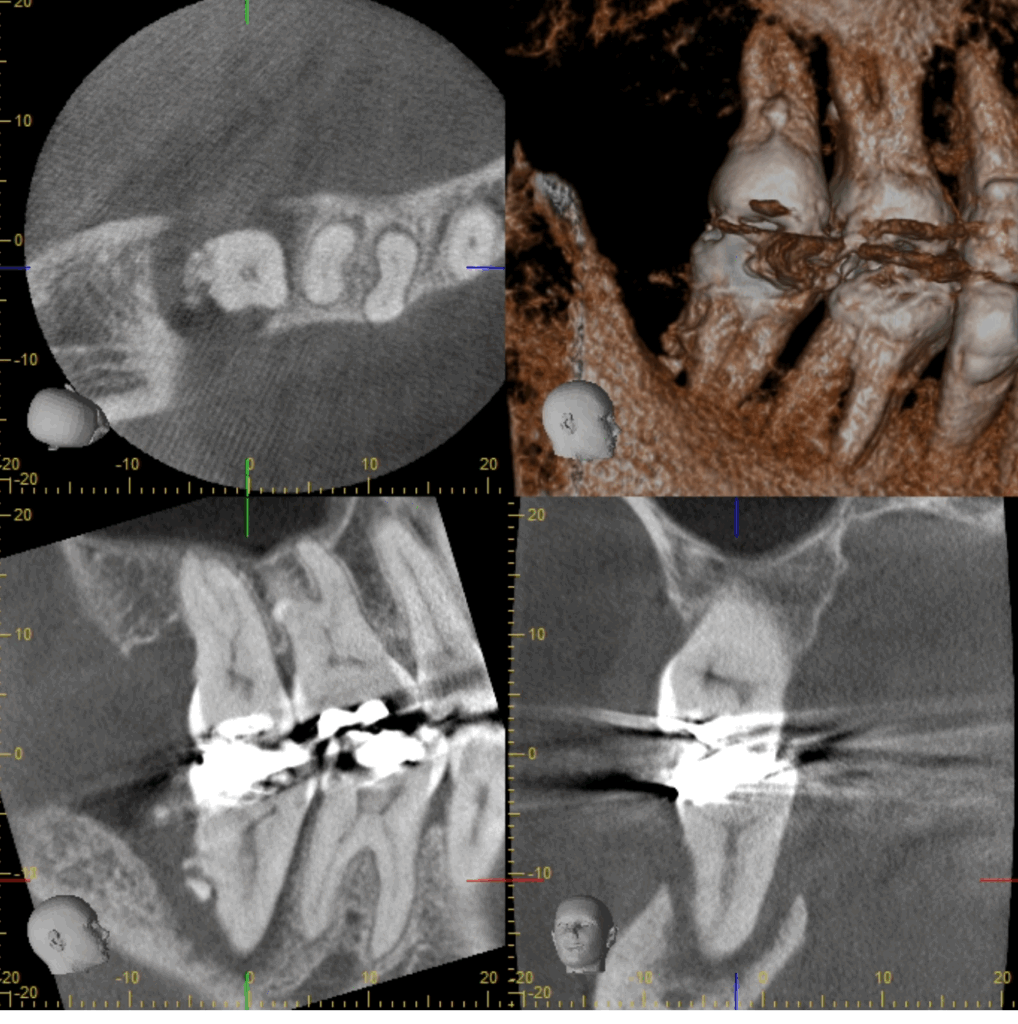

- 歯科用CT:三次元で骨や根管の形態を正確に把握

結果としてレントゲンでは「黒い影」として映し出されます。

👉 臨床的には、3~6か月で黒い影が縮小し、1年前後で完全に骨が回復するケースも多くあります。

「歯茎から膿が出続けていましたが、治療後は腫れが消え、CTで骨の再生が確認できました。」